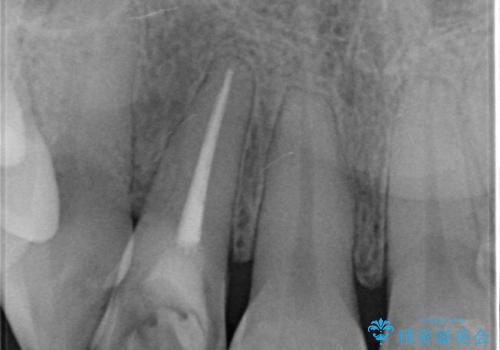

- 右上前歯の形と色が気になるとのことで来院された患者様です。

残っている歯に亀裂が多く走っていたため、クラウンでの修復処置を行います。

- 右上2 仮歯/11,000円 ファイバーコア/22,000円 ジルコニアクラウン(スタンダード)/121,000円 合計154,000円費用は治療当時の料金となります